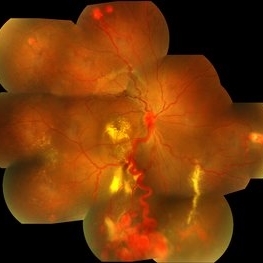

This is a patient who presented with retinal angiomas due to Von Hippel Lindau Syndrome

Fundus photograph of a patient with Von Hipple Lindau Disease and retinal angiomas.

Photographer: Avris Siahaan, Klinik Mata Nusantara